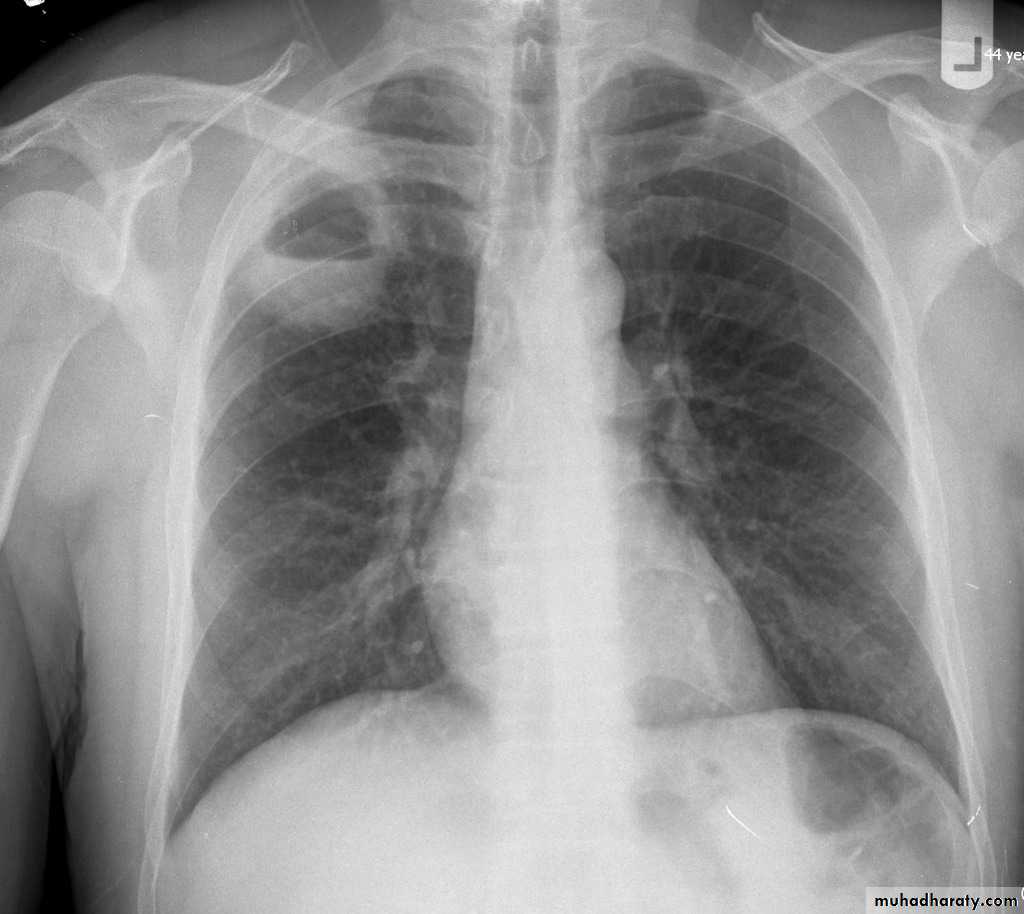

Right upper lobe collapse has distinctive features, and is usually easily identified on frontal chest radiographs .

Radiographic features

Chest radiograph

Collapse of the right upper lobe is usually relatively easy to identify on frontal radiographs. Features consist of :

increased density in the upper medial aspect of the right hemithorax

elevation of the horizontal fissure

loss of the normal right medial cardiomediastinal contour

elevation of the right hilum

hyperinflation of the right middle and lower lobe result in increased translucency of the mid and lower parts of the right lung

right juxtaphrenic peak

A common cause of lobar collapse is a hilar mass. When a right hilar mass is combined with collapse of the right upper lobe, the result is an S shape to elevated horizontal fissure. This is known as Golden S sign .

Non-specific signs indicating right sided atelectasis are also usually present including:

elevation of the hemidiaphragm

crowding of the right sided ribs

shift of the mediastinum and trachea to the right